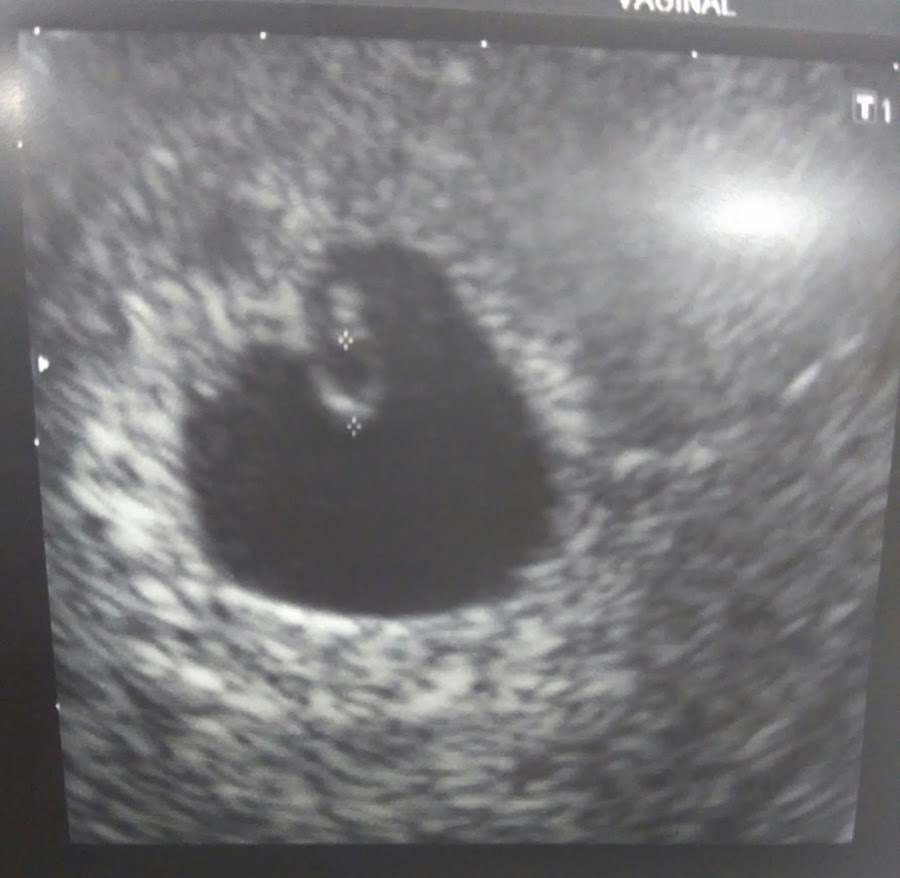

Pero no hizo falta, según me tumbé en el potro, lo encontró, y a pesar de estar en la semana 6 yo misma pude ver su corazoncito moverse, intentó buscar el sonido diciendo que sería difícil, pero lo escuchamos, bajito, pero ahí estaba. Se me saltaron las lágrimas.

Voy a permitirme hacerme ilusiones con una cosa. Y se trata del método Ramzi de predicción del sexo del bebé por su posición en el útero.

Niña: a la izquierda.

Niño: a la derecha.

¿Que opinas? ¿Voy comprando cosas rositas? El tiempo lo dirá.